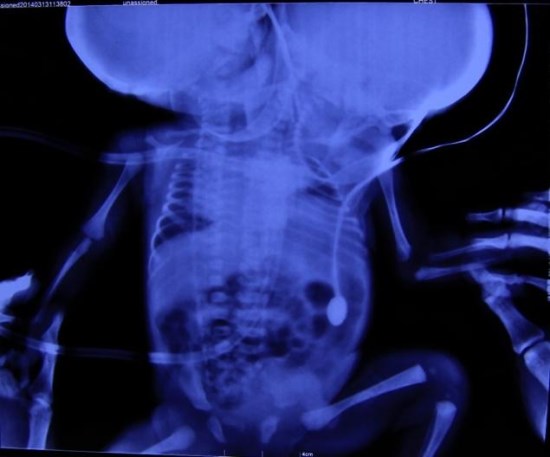

A médica que fez o parto dos gêmeos a Dra. Shikha Malik, informou que eles nasceram com duas cabeças, dois pescoços, duas espinhas cerebrais e esôfagos e traquéia separados, mas eles têm apenas um coração e estômago e um pulmão cada.

Ela disse ainda que a maioria dos seus orgãos são compartilhados. Na maioria das vezes quando um bebê está dormindo, o outro está chorando e por enquanto o lado direito está cresendo muito mais forte.